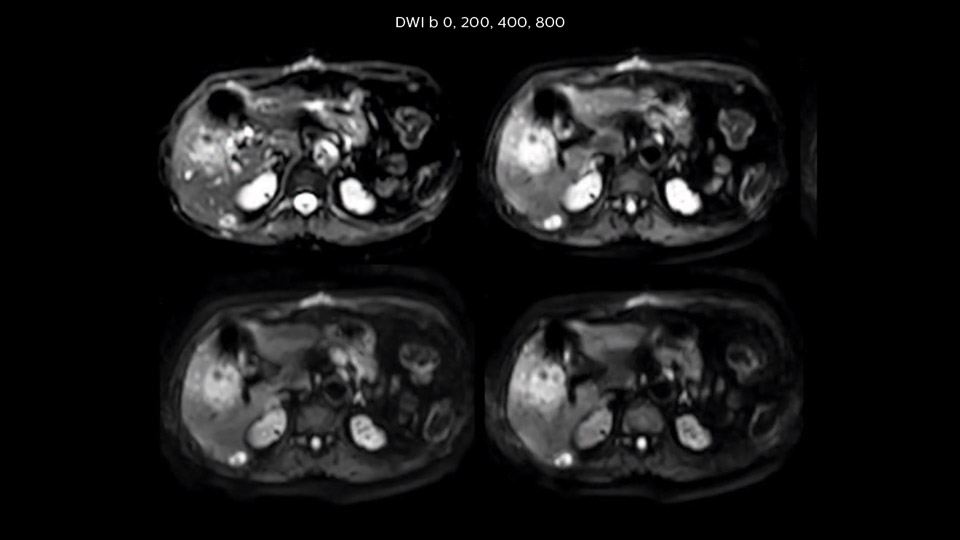

“Our liver exams are quite fast,” says Dr. Baumann. “If the patient tolerates it, we use an arms-up position to reduce the FOV and speed up the exam with dS SENSE.” “We acquire one transversal high resolution T2-weighted sequence with 3 mm slice thickness, for example for pancreas or liver lesions. Then we also add a T2 fat suppressed MultiVane XD SPIR sequence. We perform these two routinely in our liver imaging. We use high dS SENSE factors to significantly shorten scan times to 2-4 minutes, which can improve our protocol; it’s a very robust scan.” “We include mDIXON for the dynamic sequences because of the robust and homogeneous fat suppression we get with that. We had been using eTHRIVE, but we are now quite happy with mDIXON. Sometimes we use a medication to calm the bowels, to further improve the image quality.”